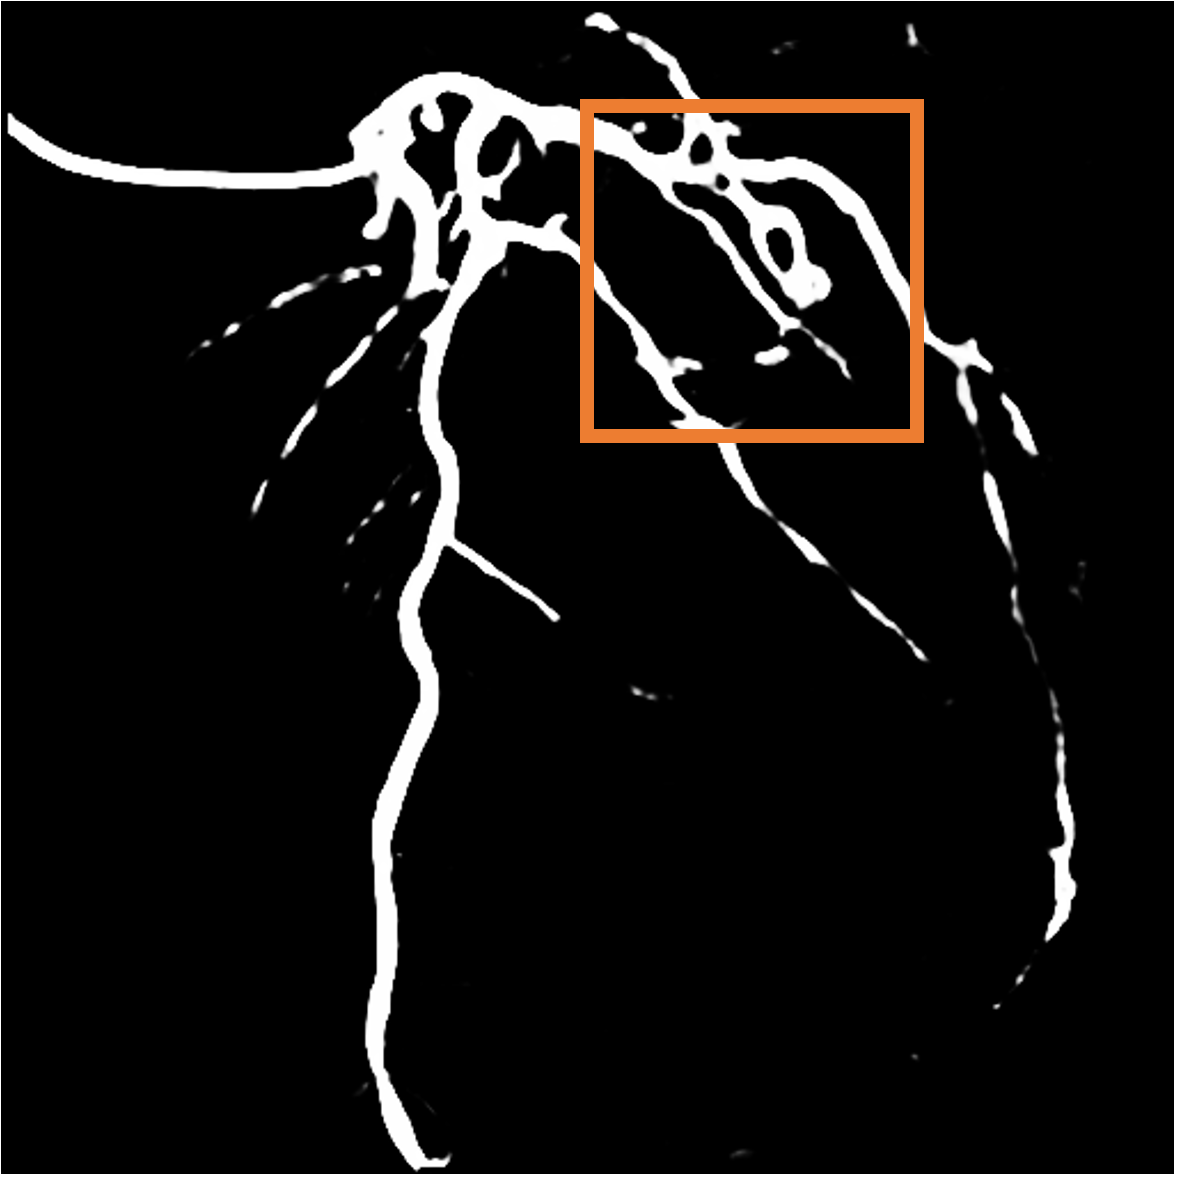

Foreground motion fields. As for the foreground, we observe that the contrast agent flows out from the catheter. Therefore, we consider the Eulerian motion field, as shown in Fig. 3, to be a more reasonable specification of blood flow behavior compared to the traditional motion field.

Parallel loss. Clearly, the direction of blood flow should align with the course of blood vessels (Fig. 4). Hence, we design the parallel loss to achieve a parallel alignment between them. Initially, we conduct skeletonization and distance transform on the masks obtained from Sec. 3.1, and calculate pixel-wise cosine similarity between these transformed masks and the predicted flow: